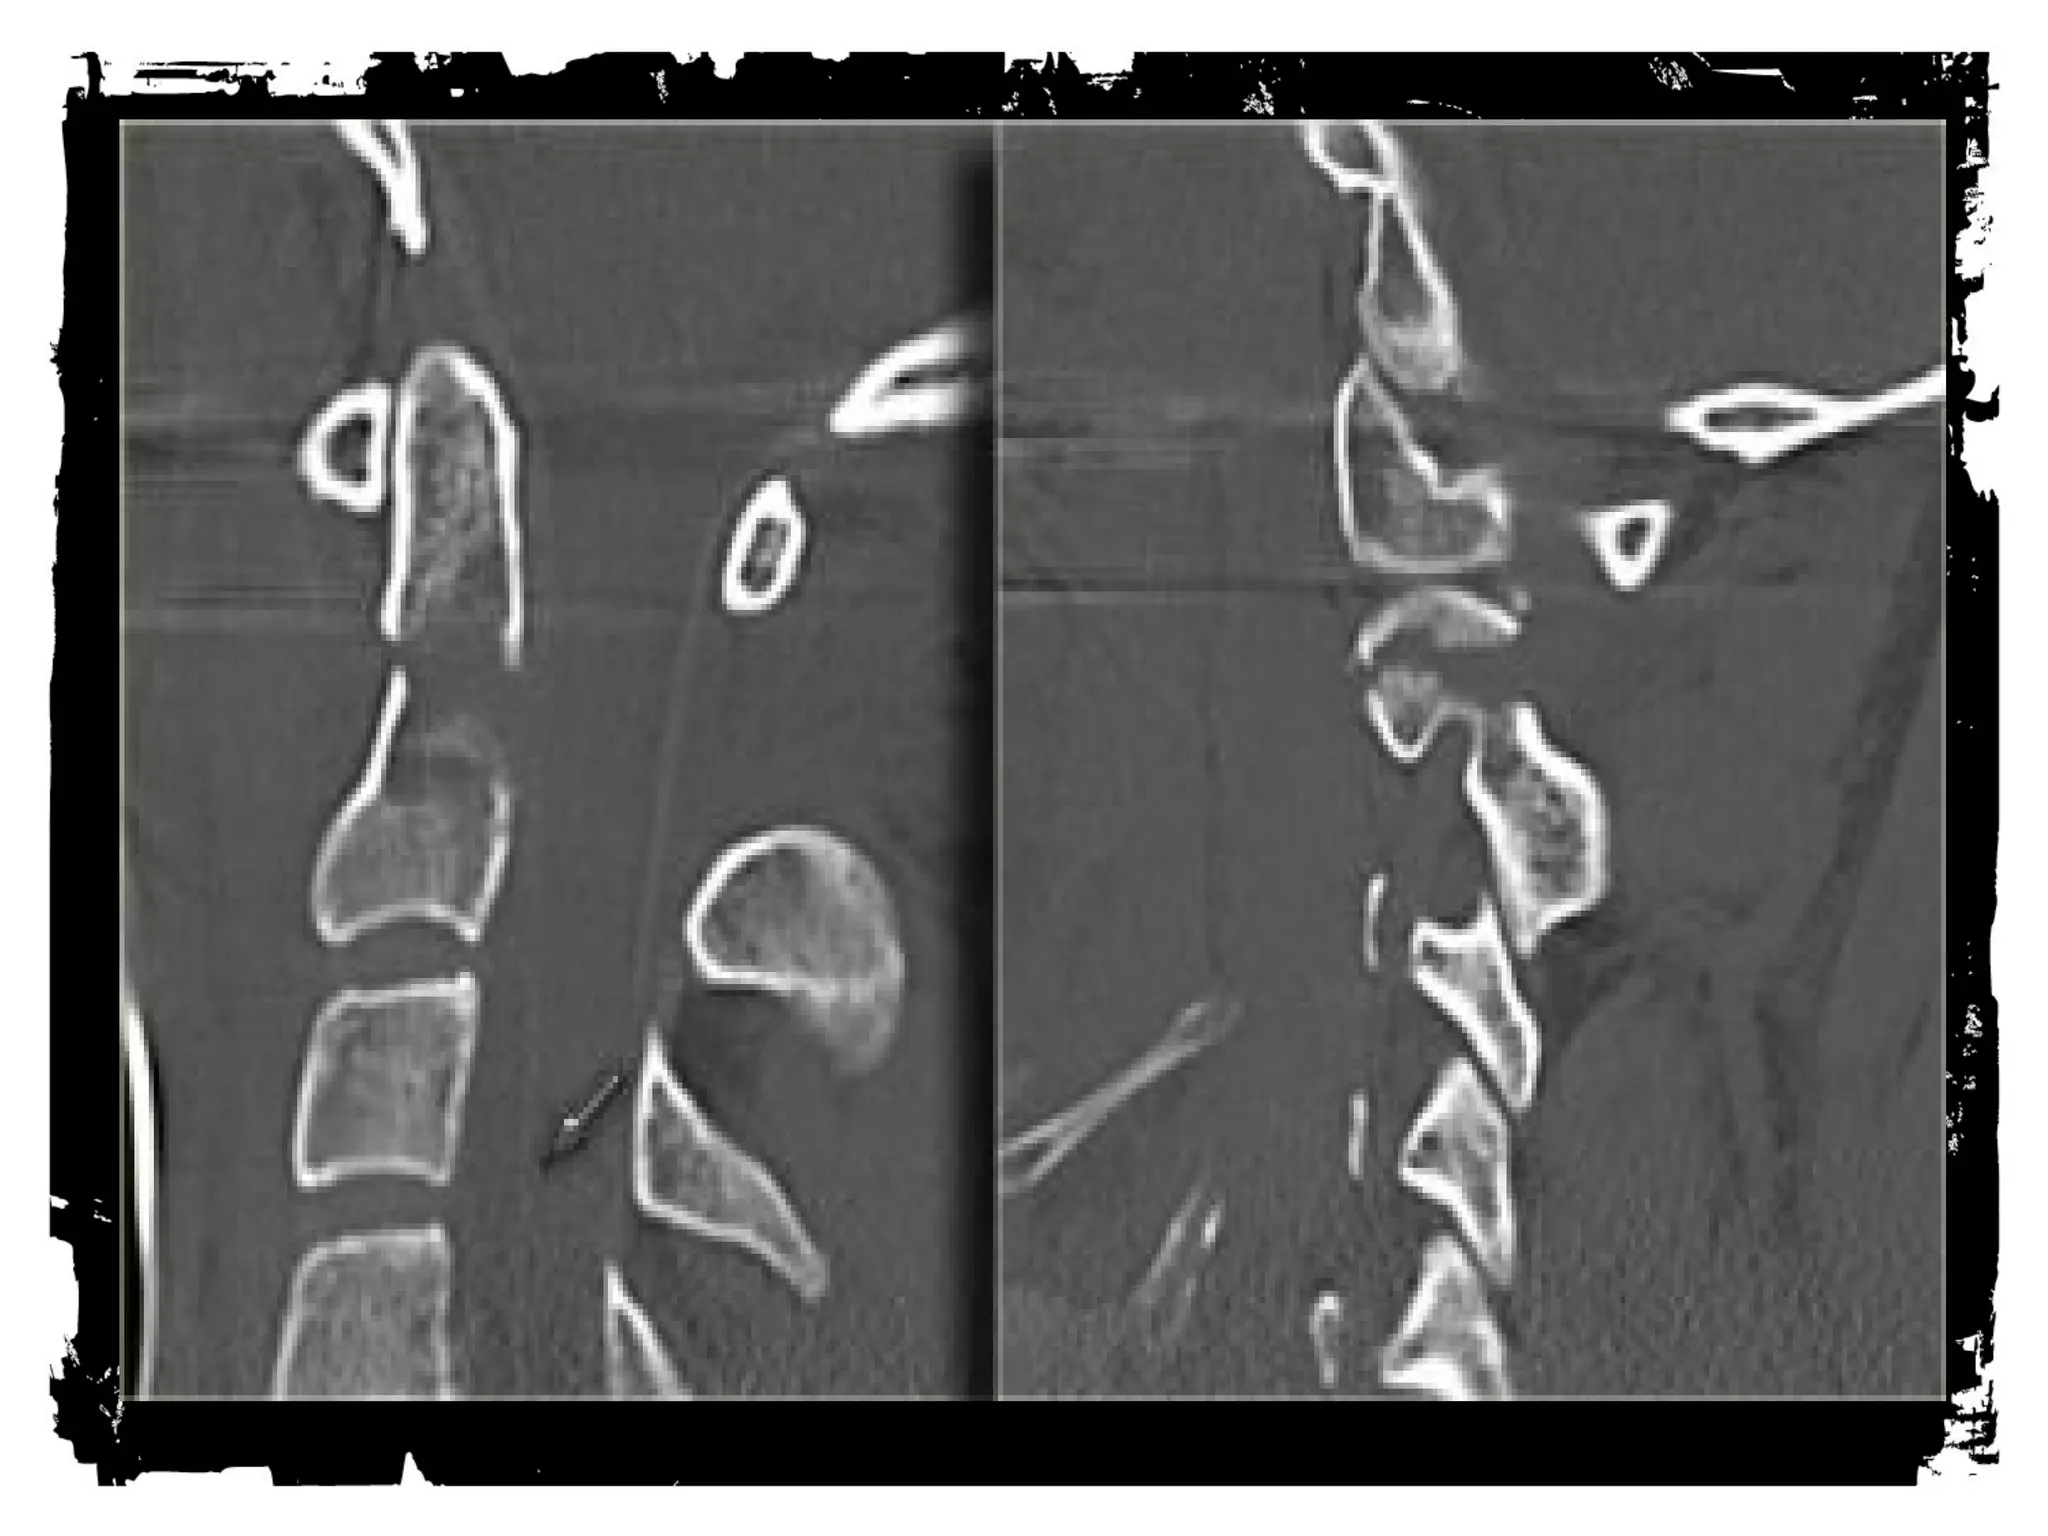

• Spine Injuries

• Look for loss of

alignment, fractures and

paraspinal hematoma.

• The findings may be very

subtle.

• CT is the imaging

modality of choice for

evaluation of these

injuries.